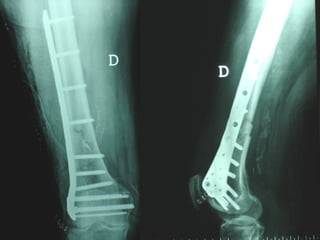

Dal Gennaio 2000 al Febbraio 2006 abbiamo trattato 167 fratture chiuse  con placca percutanea  in 164 pazienti :  27 lesioni diafisarie di gamba, 12 piloni tibiali ,  11 fratture prossimali di tibia, 36 fratture sovracondiloidee di femore, 17 fratture diafisarie di femore, 43 fratture metaepifisarie prossimali di omero, 21 diafisarie d’omero.  156 guarigioni 8 fallimenti

Dal Gennaio 2000 al Dicembre 2005 27 placche LISS di femore

INDICAZIONI COMUNI Fratture sovracondiloidee Fratture intercondiliodee Fratture diafisarie distali PARTICOLARI Fratture con grave osteoporosi Fratture periprotesiche

VANTAGGI CHIRURGIA MININVASIVA Mini Open Inserimento della placca sottocutaneo per scivolamento Viti percutanee Preservazione dei tessuti molli Ridotto danno vascolare Rapida ripresa funzionale